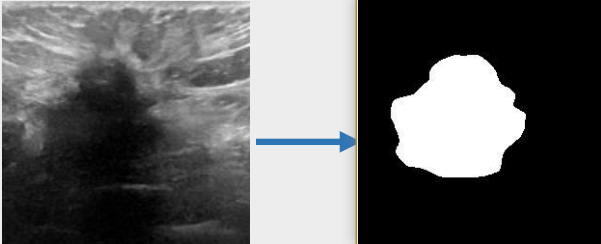

## 算法原理 U-KAN与其它图像分割算法一样,将图片数据送入模型后,依次通过预处理、特征提取,最后经过卷积预测出像素类别实现分割。

## 环境配置 ``` mv U-KAN_pytorch U-KAN # 去框架名后缀 # if torch>2.0, modify /usr/local/lib/python3.10/site-packages/timm/models/layers/helpers.py: from torch._six import container_abcs -> import collections.abc as container_abcs ``` ### Docker(方法一) ``` docker pull image.sourcefind.cn:5000/dcu/admin/base/pytorch:2.1.0-ubuntu20.04-dtk24.04.1-py3.10 # 为以上拉取的docker的镜像ID替换,本镜像为:a4dd5be0ca23 docker run -it --shm-size=32G -v $PWD/U-KAN:/home/U-KAN -v /opt/hyhal:/opt/hyhal:ro --privileged=true --device=/dev/kfd --device=/dev/dri/ --group-add video --name ukan bash cd /home/U-KAN pip install -r Seg_UKAN/requirements.txt # requirements.txt ``` ### Dockerfile(方法二) ``` cd U-KAN/docker docker build --no-cache -t ukan:latest . docker run --shm-size=32G --name ukan -v /opt/hyhal:/opt/hyhal:ro --privileged=true --device=/dev/kfd --device=/dev/dri/ --group-add video -v $PWD/../../U-KAN:/home/U-KAN -it ukan bash # 若遇到Dockerfile启动的方式安装环境需要长时间等待,可注释掉里面的pip安装,启动容器后再安装python库:pip install -r Seg_UKAN/requirements.txt。 ``` ### Anaconda(方法三) 1、关于本项目DCU显卡所需的特殊深度学习库可从光合开发者社区下载安装: - https://developer.hpccube.com/tool/ ``` DTK驱动:dtk24.04.1 python:python3.10 torch:2.1.0 torchvision:0.16.0 ``` `Tips:以上dtk驱动、python、torch等DCU相关工具版本需要严格一一对应。` 2、其它非特殊库参照requirements.txt安装 ``` pip install -r Seg_UKAN/requirements.txt # requirements.txt ``` ## 数据集 `BUSI(Breast Ultrasound Image)` - https://www.kaggle.com/datasets/aryashah2k/breast-ultrasound-images-dataset 本项目无需下载原始数据集,采用U-KAN作者提供的预处理数据[pre-processed dataset](https://mycuhk-my.sharepoint.com/:f:/g/personal/1155206760_link_cuhk_edu_hk/ErDlT-t0WoBNlKhBlbYfReYB-iviSCmkNRb1GqZ90oYjJA?e=hrPNWD) 即可。 项目中已包含[`busi`](./Seg_UKAN/inputs/busi.zip),解压即可使用,训练数据目录结构如下: ``` Seg_UKAN ├── inputs │ ├── busi │ ├── images │ ├── malignant (1).png | ├── ... | ├── masks │ ├── 0 │ ├── malignant (1)_mask.png | ├── ... ``` 数据集快速下载中心:SCNet AIDatasets ,项目中预处理数据集可从快速下载通道下载:[busi_cvc_glas_preprocessed](http://113.200.138.88:18080/aidatasets/project-dependency/busi_cvc_glas_preprocessed.git) 。 ## 训练 ### 单机单卡 ``` # 以公开数据集busi为基础进行算法效果优化 cd Seg_UKAN python train.py --arch UKAN --dataset busi --input_w 256 --input_h 256 --name busi_UKAN --data_dir ./inputs ``` 更多资料可参考源项目的[`README_origin`](./README_origin.md) ## result

### 精度 数据集:busi,max epoch为400,训练框架:pytorch。 | device | Dice | |:---------:|:-------:| | DCU K100 | 78.75% | | GPU V100S | 78.75% | ## 应用场景 ### 算法类别 `图像分割` ### 热点应用行业 `医疗,电商,制造,能源` ## 源码仓库及问题反馈 - http://developer.hpccube.com/codes/modelzoo/u-kan_pytorch.git ## 参考资料 - https://github.com/CUHK-AIM-Group/U-KAN.git - https://github.com/KindXiaoming/pykan.git - https://kindxiaoming.github.io/pykan/